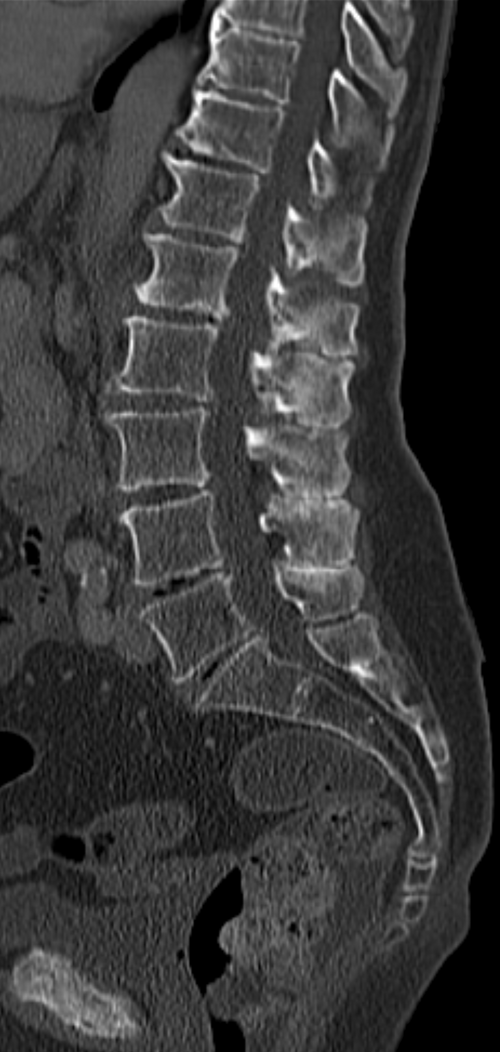

Thoracolumbar compression fracture (T12) with vertebral body height loss, retropulsed fragment, marrow edema, and...